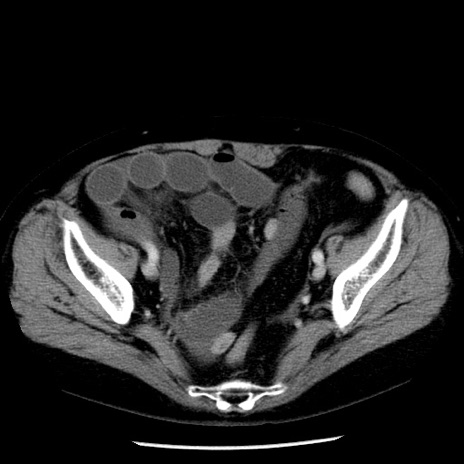

症例13(横断像)

【症例】70歳代女性

【主訴】腹痛、嘔吐

【現病歴】15時間程前(昨晩)より腹痛あり。今朝になっても症状の改善なく、嘔吐あり。腹痛も増悪あり、救急外来受診。

【既往歴】子宮癌全摘術後

【身体所見】意識清明、BP 121/72mmHg、P 74bpm、SpO2 100%(RA)、腹部:平坦・軟、腸雑音ほぼ聴取せず。下腹部・心窩部・臍左上に圧痛あり。反跳痛なし。

【データ】WBC 10600、CRP 0.15